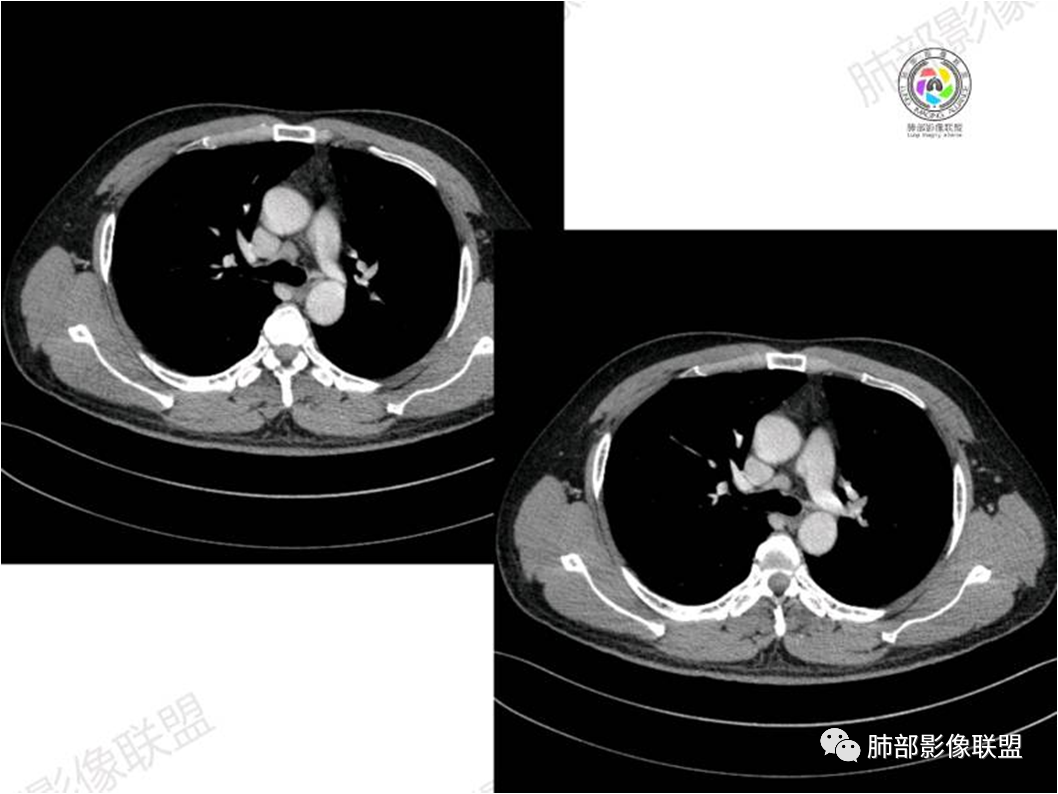

黏膜相关淋巴组织(Mucosa associated lymphoid tissue, MALT)淋巴瘤是来源于黏膜相关淋巴 组织边缘带的低度恶性非霍奇金B细胞淋巴瘤。肺MALT淋巴瘤较为罕见,约占淋巴瘤的0.14%~1%,易被误诊为肺炎或肺癌。

MALT淋巴瘤这一概念最早由Isaacson和 Wright等于1983年提出,其可发生全身具有黏膜的器官或组织,最常见于胃肠道,其次为肺(15%)组织,病因不明,目前多认为与慢性感染、吸烟或自身免疫性疾病有关。肺MALT淋巴瘤是较为罕见的低度恶性肿瘤,多见于50-70岁,男女发病率无明显差异,或男性略多于女性。

MALT淋巴瘤影像表现为实变、结节及磨玻璃影,其中实变是其特点,胸膜下或支气管血管束节段性分布具有特征性,跨叶征较常见,这可能与肿瘤细胞进入血循环后往往又回到上皮黏膜部位,它们从一处黏膜到另一处黏膜,但不会到外周淋巴组织等有关。国外多名学者的影像-病理研究报道认为其病理学基础是由于肿瘤细胞沿支气管血管束周围间质及胸膜浸润生长,形成小叶间隔增厚、支气管血管束增粗等间质性改变,进一步浸润肺泡壁、充填肺泡腔。

①实变的出现率100%,多表现为两(89%)或单肺多发,密度均匀,与邻近胸壁肌肉的密度大致相等,少见钙化(15%),这与病灶内血管保持 完整,血供丰富,且肿瘤生长缓慢,对缺氧耐受好,不易坏死有关。边缘磨玻璃影或晕征具有特异性,其病理学基础是肿瘤细胞对小叶间隔、肺泡壁的淋巴瘤样浸润;

⑥肺门及纵隔淋巴结肿大少见;

肺MALT淋巴瘤需要与大叶性肺炎、肺结核、肺癌及继发性淋巴瘤等鉴别。大叶性肺炎多有高热症状,CT多表现为单个肺叶实变影,很少跨叶分布,充气支气管管径及形态正常。肺结核多有低热、盗汗症状,多发生于两肺上叶尖段及下叶背 段,多可见长毛刺、钙化或空洞,周围常见卫星灶,结核菌素试验阳性。肺炎型肺癌临床症状常较轻,部分因含量黏液而密度偏低,充气支气管可呈扭曲不规则狭窄、中断。肺癌CT表现为肺部肿块,可有分叶、毛 刺征、空泡征、血管集束征及胸膜凹陷征,肿块可有支气管中断、闭塞,可伴有肺门及纵隔淋巴结肿大。继发性淋巴瘤有肺外淋巴瘤的表现,除肺内病变外,常有肺门及纵隔淋巴结肿大。